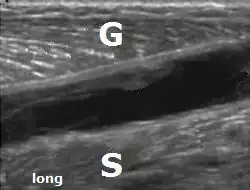

Door middel van echografisch onderzoek ('echo' of musculoskeletale echografie) is een tenniskuit duidelijk te herkennen en te onderscheiden van de rupturen. Hier twee verschillende echografische afbeeldingen van een vochtcollectie, kennelijk een hematoom (zwart, echoarm deel) tussen de musculus gastrocnemius en de musculus soleus (diepe kuitspier).

G= musculus gastrocnemius, S= musculus soleus.